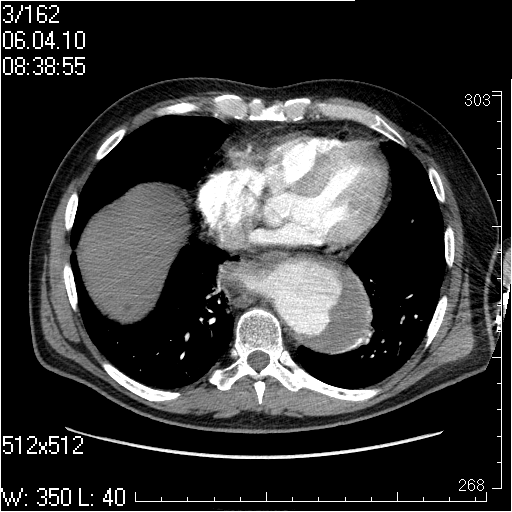

Грудной отдел аорты

Пожилой мужчина, жалоб в настоящее время не предъявляет.